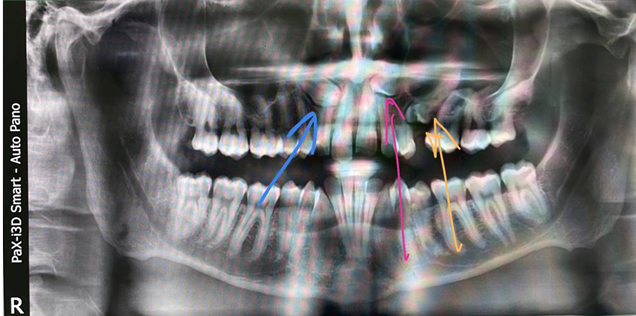

Тут у пациента постоянные клыки и непрорезавшиеся премоляры в верхней челюсти:

А вот ещё более интересный случай. Мы все знаем истории про восьмые зубы, которые уже атавизм. Вот даже пост про них. А тут ещё интереснее:

Справа у пациента есть целый девятый зуб! Это жёлтая стрелка. А синяя стрелка показывает девятый непрорезанный. Девятый зуб поставляется со своим сосудом и нервом. Он имеет все органы и ткани, как у здорового зуба. Он уже с момента образования зачатка соединён с нервной системой, там сосудисто-нервный пучок. Делать с этими зубами пока ничего не надо, надо наблюдать.